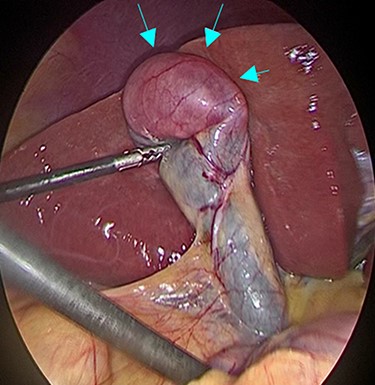

Intraoperative findings during laparoscopic cholecystectomy; The tumor was at fundus of gallbladder without serosal invasion.

A 53-year-old man with history of liposarcoma had gallbladder tumor detected during routine ultrasonography (Fig. 1A) and was referred to us. He was first diagnosed as leg liposarcoma 5 years before and underwent complete resection. Despite of history of liposarcoma in his leg, he never developed any abdominal symptoms. Laboratory tests were unremarkable including carcinoembryonic antigen and carbohydrate antigen 19-9 (CA19-9) within their normal limits. Computed tomography (CT) scan demonstrated slightly enhanced 4-cm tumor located at gallbladder fundus (Fig. 1B). On magnetic resonance imaging (MRI), the tumor had high signal in both of T2 and diffusion weighed image and low signal in both of T1 and apparent diffusion coefficient (Fig. 1C–F). Based on these findings in imaging studies, our working differential diagnosis included liposarcoma and hemangioma rather than adenocarcinoma, and we recommended laparoscopic cholecystectomy. In the exploration, the tumor in the fundus appeared without serosal invasion (Fig. 2). Intraoperative ultrasonography revealed the tumor was contained in the gallbladder without infiltration into the liver, and in fact there was a distance between the liver bed and the tumor. Sonazoid enhanced ultrasonography ruled out liver metastasis and thus, we proceeded to laparoscopic cholecystectomy as planned. When the gallbladder was opened, yellowish white tumor was confirmed in the submucosal layer with the overlying mucosa intact (Fig. 3A). Histopathological examination revealed, this tumor as myxoid liposarcoma consisting of lipoblasts and round cells. There was no necrosis and proliferations of spindle and round cell component were identified in the background of myxoid stroma (Fig. 3B). These histological features were similar to the ones for the sarcoma in his leg that was resected before. The patient’s postoperative course was uncomplicated and was discharged home on Day 3. The adjuvant therapy was elected not to be given and he was placed on imaging surveillance with CT scan in every 3–6 months. In 16 months after this operation, he developed disease recurrence in the left popliteal fossa. There was no recurrence to date in the abdominal cavity at 28 months after the operation, he was alive with disease.